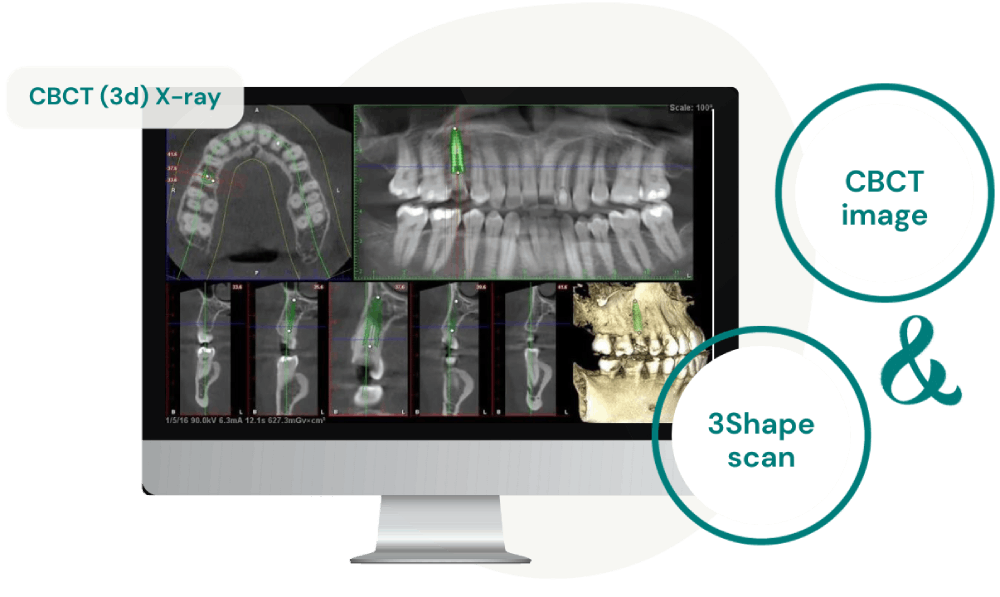

CBCT-Bild und 3Shape-Scan

Wir verwenden eine Kombination aus CBCT-Bildern und 3Shape-Scans, um eine individuelle chirurgische Schablone für präzise Implantatplatzierung zu erstellen.

Die Cone Beam Computertomographie (CBCT) ist eine spezialisierte Bildgebungstechnologie, die detaillierte dreidimensionale Ansichten der Kieferstrukturen bietet, mit der wir äußerst präzise und detaillierte Bilder der oralen und maxillofazialen Strukturen erfassen können. Diese Bilder werden verwendet, um einen Implantattherapieplan zu erstellen. Mit diesem individuell erstellten Plan fertigen wir eine chirurgische Schablone an, die die Grundlage für die Installation der Implantate bildet.